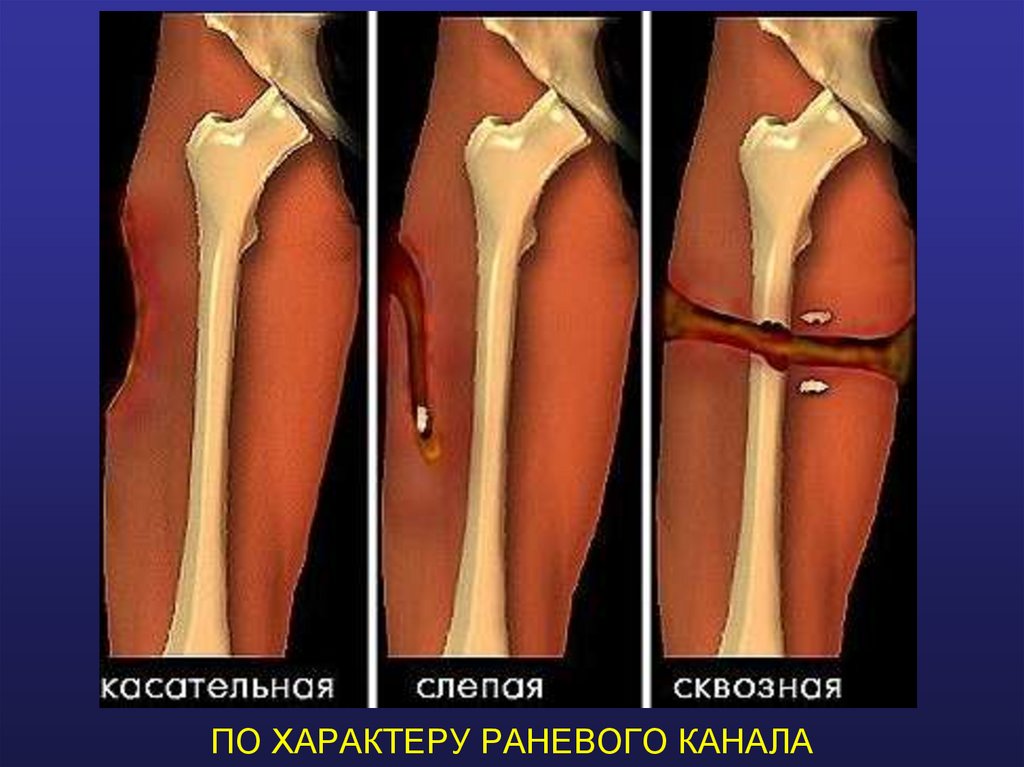

ПО ХАРАКТЕРУ РАНЕВОГО КАНАЛА

33. ПО ХАРАКТЕРУ РАНЕВОГО КАНАЛА